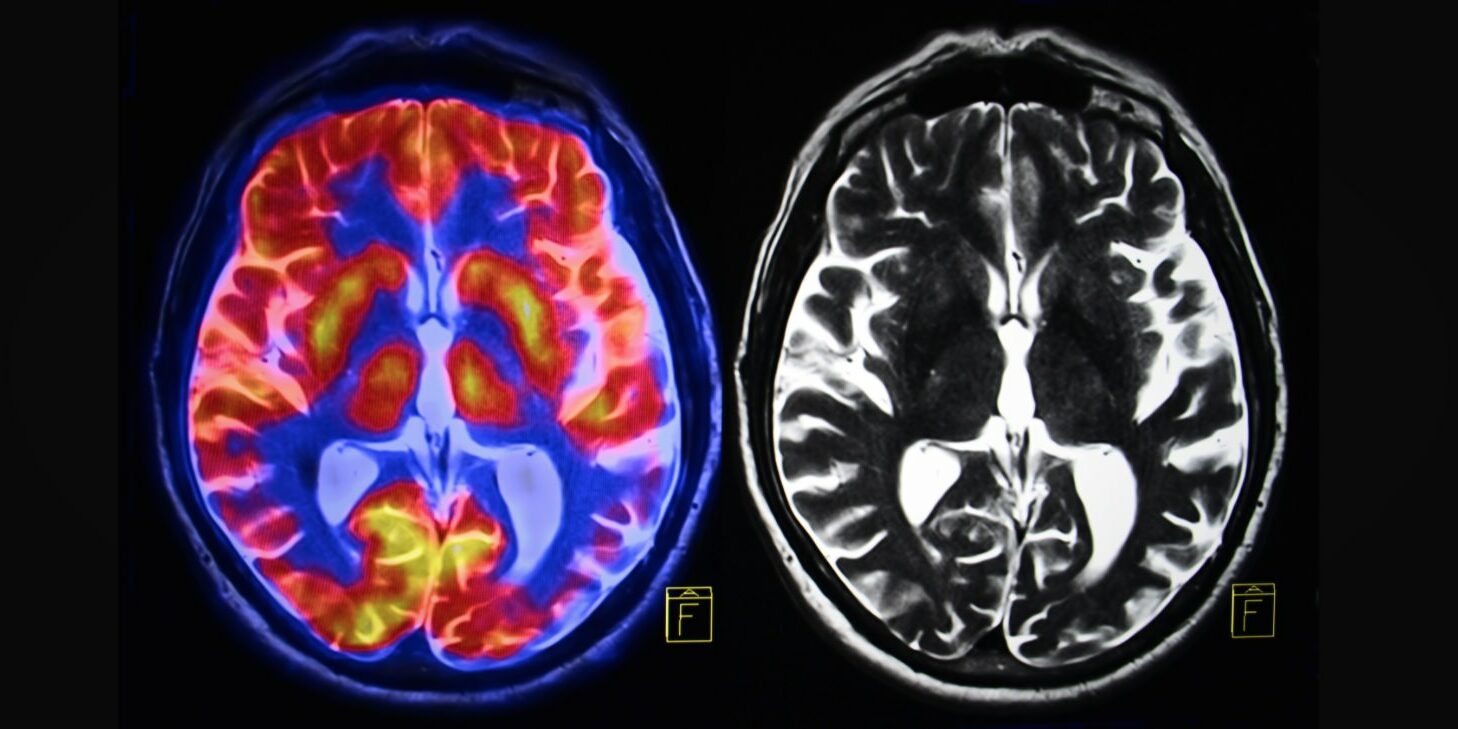

1. Une fois que vous arrêtez la pornographie, les voies cérébrales qu’elle a créées commencent à s’effacer.

Plus on emprunte un chemin, plus il se creuse. Avec une addiction, c’est pareil. A chaque consommation, la voie cérébrale associée est renforcée.

Au fur et à mesure que le consommateur s’éloigne de la pornographie, les voies cérébrales liées à l’addiction vont rétrécir et elles vont, à terme, lui faire perdre l’envie de consommer. Ce sera lent, mais cela se produira.

3. Le cerveau peut retrouver sa sensibilité à des activités quotidiennes saines.

L’une des principales parties de votre cerveau qui est affectée par la consommation de pornographie est le centre de récompense. Lorsque ce centre est surutilisé, il produit moins de « substances chimiques du plaisir » (dopamine, sérotonine, adrénaline, etc.) et y réagit moins. Il faut donc toujours plus de stimulation pour que le consommateur de porno se sente bien.

Si le porno est éliminé, le cerveau du consommateur cherchera de nouvelles sources de récompense. Les anciens accros pourront alors se concentrer sur de nouvelles activités plus saines comme le sport.

4. Les recherches indiquent que les lobes frontaux endommagés peuvent se rétablir une fois que la surstimulation constante cesse.

L’addiction peut provoquer des changements néfastes dans le cerveau, dont le plus courant est le rétrécissement du lobe frontal. C’est grave car les lobes frontaux du cerveau sont la partie qui s’occupe principalement du choix, de la logique et du raisonnement. C’est comme si les consommateurs n’avaient pas la partie de leur cerveau qui les aide à faire des choix sains. C’est pourquoi les consommateurs fréquents – même ceux qui veulent arrêter – reviennent sans cesse à des comportements non désirés.